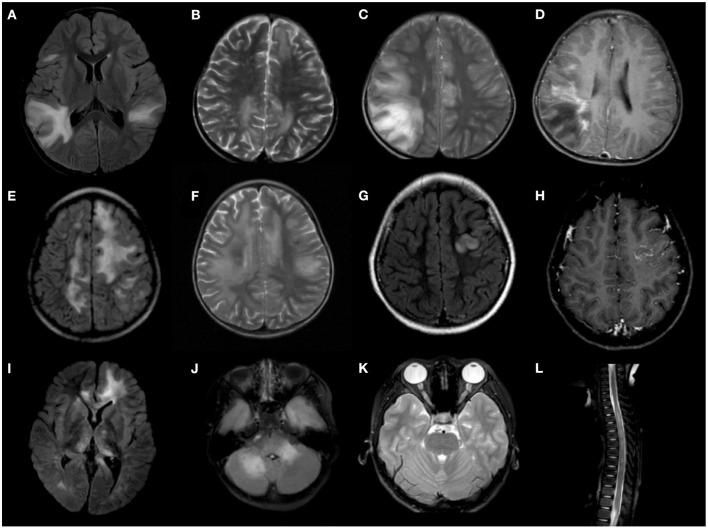

To analyze the positive and recurrence rates of different autoantibody-associated demyelination disorders in children in Southwest China, and describe the clinical, radiological, and prognostic features of the myelin oligodendrocyte glycoprotein antibody (MOG-ab) and aquaporin-4 antibody (AQP4-ab) associated disease. This study also summarizes steroid maintenance therapy approaches for MOG-ab-positive children. A total of 160 children presenting with acquired demyelinating syndromes (ADS) between January 2016 and December 2019 were tested for MOG-ab and AQP4-ab. Clinical data, MRI scans, and survival analyses were compared between MOG-ab-positive and AQP4-ab-positive children. Evolution of serologic status and treatment response to immunosuppressants were collected in MOG-ab-positive children. Of the 160 included children, the MOG-ab positivity rate (47.4%) was significantly higher than the AQP4-ab (5%) positivity rate. The recurrence rate for AQP4-ab disease (71.4%) was higher than that of MOG-ab disease (30.1%). For 135 children with both MOG-ab and AQP4-ab tested, the median age at onset was 7 (interquartile range [IQR] 5-10) years, and the median follow-up period was 19 (IQR 13-27.5) months. MOG-ab-positive children more frequently presented with acute disseminated encephalomyelitis, had deep gray matter lesions on MRI, had a better clinical and radiological recovery, and were less likely to have sustained disability than AQP4-ab-positive children. In MOG-ab-positive and AQP4-ab-positive children, maintenance therapy was a protective factor for recurrence, but presenting optic neuritis was a predictor of earlier relapse. A high Expanded Disability Status Scale score at onset was associated with sustained disability. Steroid maintenance therapy longer than 6 months after the initial attack was associated with a lower risk of a second relapse in MOG-ab-positive children. On serial serum MOG antibody analysis, clinical relapse occurred in 34.6% of children with persistent seropositivity, but none of the children who converted to seronegative status experienced relapse. The MOG antibody is more common in children with ADS than the AQP4 antibody. MOG-ab-positive children are characterized by distinct clinical and radiological features. Although some MOG-ab-positive children experience relapsing courses or have persistently seropositive status, they still predict a better outcome than AQP4-ab-positive children.

分析中国西南地区儿童不同自身抗体相关脱髓鞘疾病的阳性率和复发率,描述髓鞘少突胶质细胞糖蛋白抗体(MOG-ab)和水通道蛋白4抗体(AQP4-ab)相关疾病的临床、影像学及预后特征。本研究还总结了MOG-ab阳性儿童的激素维持治疗方法。对2016年1月至2019年12月期间共160例出现获得性脱髓鞘综合征(ADS)的儿童进行了MOG-ab和AQP4-ab检测。比较了MOG-ab阳性和AQP4-ab阳性儿童的临床资料、MRI扫描结果及生存分析。收集了MOG-ab阳性儿童的血清学状态演变及免疫抑制剂治疗反应情况。在纳入的160例儿童中,MOG-ab阳性率(47.4%)显著高于AQP4-ab阳性率(5%)。AQP4-ab相关疾病的复发率(71.4%)高于MOG-ab相关疾病(30.1%)。在135例同时检测了MOG-ab和AQP4-ab的儿童中,发病年龄中位数为7(四分位间距[IQR]5 - 10)岁,中位随访时间为19(IQR 13 - 27.5)个月。与AQP4-ab阳性儿童相比,MOG-ab阳性儿童更常表现为急性播散性脑脊髓炎,MRI上有深部灰质病变,临床和影像学恢复较好,且持续残疾的可能性较小。在MOG-ab阳性和AQP4-ab阳性儿童中,维持治疗是复发的保护因素,但出现视神经炎是早期复发的预测因素。发病时高扩展残疾状态量表评分与持续残疾相关。首次发作后激素维持治疗超过6个月与MOG-ab阳性儿童第二次复发风险较低相关。在系列血清MOG抗体分析中,持续血清阳性的儿童中有34.6%发生临床复发,但转为血清阴性的儿童均未复发。与AQP4抗体相比,MOG抗体在ADS儿童中更常见。MOG-ab阳性儿童具有独特的临床和影像学特征。尽管一些MOG-ab阳性儿童经历复发病程或血清持续阳性,但他们的预后仍比AQP4-ab阳性儿童好。